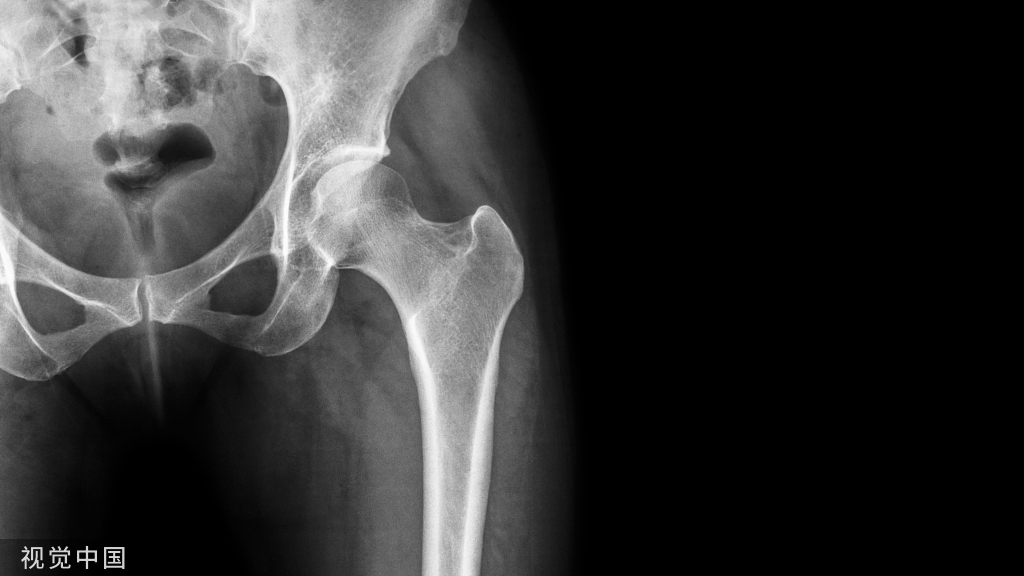

股骨干骨折复位固定的适应症,主要是股骨干部骨折,即指股骨小粗隆以下 2~5cm和 股骨髁上2~5cm的干部骨折。

在使用中根据大腿的解剖特点、骨折类型、移位程度和方向,在骨折部上、下端各穿一根骨针,而后视残余移位或再移位的倾向,在骨折上段或下段加半根针,纠正残余移位,有效的控制再移位的倾向,维持骨折断端的稳定。

遵照穿针外 固定的穿针原则,穿针时一定要确认安全区, 避免损伤股动、静脉、股神经和隐神经、大隐静脉。

安全区的选择

由于大腿的解剖生理特点,股骨干为人体内最大的长管状骨,坚强而粗大,周围有强有力的肌群包绕。在股前区上部股三角内有股神经、股动脉、股静脉、腹股 沟下深、浅淋巴结及股深动、静脉等结构。股三角上界为腹股沟韧带,该韧带中心向下可触 及股动脉搏动。内界为长收肌内缘,外界为缝匠肌内缘。股三角的尖端距腹股沟韧带约 10cm,该区由于重要器官集居,故股三角区是穿针的禁区。